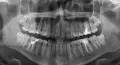

Хотелось бы узнать ваше мнение. Около года болел зуб - реагировал на холодное/горячее, ныл при соприкосновении с другими зубами. Зуб был запломбирован. Затем около зуба появилась шишка, около месяца все увеличивалась. Врач-хирург раскрыл зуб, разрезал шишку, убрал гной. Через два дня снова гнойник воспалился, потом еще через два дня. В итоге, в понедельник мне в очередной раз разрезали десну, во вторник врач стоматолог почистила канал, по рентгену сказала, очень сильное воспаление у корней зуба, поставила временную пломбу, и в среду, на следующий день, запломбировала насмерть. Сказала - дай бог все будет хорошо, до воспаления не добраться. Сегодня пятница, зуб ноет постоянно, тупая боль, сижу на обезболивающих.

Конечно, это не норма, воспаление вам не пролечили, и пломбировать каналы было нельзя. Рекомендую вам сменить доктора и обратиться к более опытным врачам. Если воспаление не удастся пролечить, то зуб вы, к сожалению, потеряете.